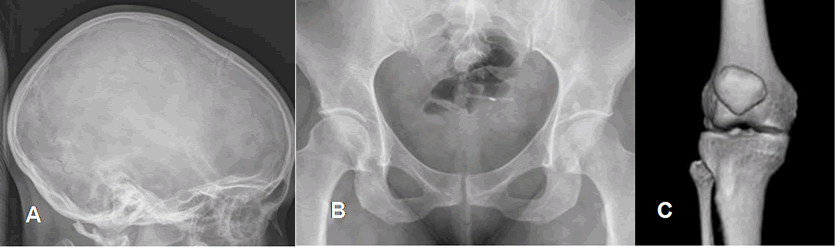

Fig 1. Tipos de articulaciones.

A: Suturas del cráneo, articulaciones fibrosas.

B: Sínfisis púbica, articulación cartilaginosa.

C: Caderas, articulaciones sinoviales.